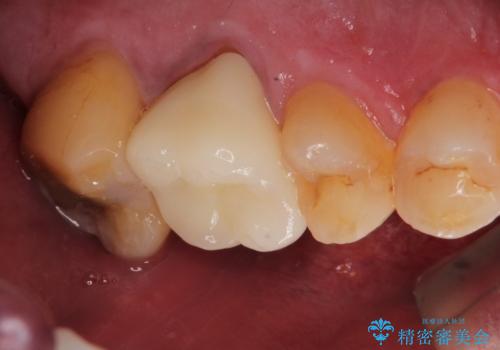

根管治療を行ったのち、症状改善を認めオールセラミッククラウンにて修復治療を行いました。

根管治療にはラバーダムシートをつけて行うことが大切です。マイクロスコープを使用し治療を行いました。治療後、歯の痛みは消失し、とても満足していただきました。

根管治療を行った歯は、再発防止や残された歯質を守るため、クラウンによる補綴治療が必要となります。